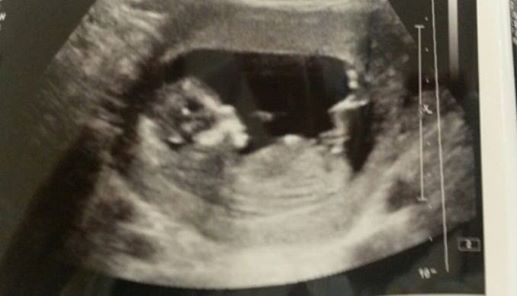

Any guesses on gender are absolutely welcome and greatfully received.

Have a gender scan booked on 5th June so will update then :)